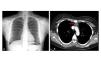

Figura 1. Evolución clínica del caso

Figura 3. Imágenes de gabinete

En su seguimiento en consulta externa alcanzó un nivel máximo de Hb 11,3 g/dl a las dos semanas de su egreso y al cumplir cuatro semanas se notó un descenso de esta hasta 9,6 g/dl, sin existir al momento una causa evidente. Se decidió seguimiento estrecho con solicitud de estudios de laboratorios para descartar causas comunes, que se comunicaron como normales, aunque con descenso progresivo de las cifras de Hb hasta 6,1 g/dl, por lo que se decidió su internamiento para estudio. Tenía una presión arterial sin cambios posturales de 105/64 mmHg, frecuencia cardíaca de 92 latidos/minuto, frecuencia respiratoria de 16 ciclos/minuto, con el único hallazgo en el examen físico de una palidez generalizada 3+/4+. Se solicitaron laboratorios de rutina, que mostraron una anemia normocítica normocrómica con reticulocitopenia severa y leve leucopenia asociada, con marcadores de hemólisis negativos, perfil de hierro normal y sin evidencia de sangrado (tabla 1, figura 1). Ante tales hallazgos, se sospechó la posibilidad de anemia por infección asociada a PVB19, se decidió reducir la inmunosupresión y cambiar de tacrolimus a ciclosporina por el potencial mielosupresivo y la asociación que ha sido comunicada; es importante mencionar que esto favoreció el incremento en la cuenta leucocitaria hasta rangos normales; además, se envió a medir la reacción en cadena de la polimerasa (PCR) cuantitativa para ADN de PVB19 en sangre periférica y se solicitó valoración a hematología, que realizó aspirado y biopsia de médula ósea, el cual se reportó con una citometría reducida en 40 %, pronormoblastos 1 %, normoblastos 2 %, blastos 0 %, neutrófilos 70 %, linfocitos 16 %, monocitos 3 %, células plasmáticas 3 %, eosinófilos 5 %, basófilos 1 %, concluyendo en una médula ósea compatible con APSR (figura 2). Ante tal diagnóstico y considerando la asociación conocida con timomas, se solicitó una tomografía torácica, en la que fue evidente una imagen isodensa en mediastino anterior de 31 x 16 x 23 mm, con densidades entre 22-34 unidades Hounsfield sin realzar con aplicación de material contrastado, sugiriendo un timoma (figura 3). La cuenta eritrocitaria continuó reduciendo hasta alcanzar un valor de Hb 3,7 g/dl, por lo que se decidió transfundir 2 paquetes eritrocitarios desleucocitados, teniendo un valor postransfusión de 7 g/dl. Una semana después se comunica PCR PVB19 con un valor de > 100 000 000 copias/ml, por lo que se decidió la administración de IGIV a 0,5 g/kg/día (27 g) durante 5 días. Con dicho tratamiento se estabilizó la Hb y luego se incrementó progresivamente en las siguientes semanas, con un valor de 12,4 g/dl a las cuatro semanas de su egreso. Durante su seguimiento en consulta externa, a los seis meses del evento ya no ha presentado reducción en la Hb, su función renal está en óptimas condiciones y con niveles de ciclosporina en rangos normales. No fue posible cuantificar nuevamente el ADN viral por motivos económicos de la paciente. Debido a la buena respuesta observada con la IGIV y la carencia de otros síntomas asociados a la aplasia, como síndrome de debilidad, se decidió un seguimiento imagenológico del timoma, con programación electiva de su cirugía a mediano plazo.